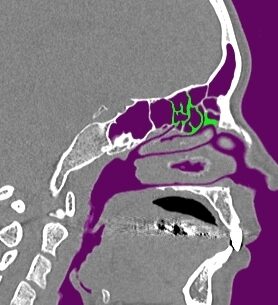

模擬手術と音響シミュレーションによる鼻副鼻腔の音響特性の解明について、現在は副鼻腔の部位の1つである上顎洞の開放範囲(切除規模)の違いによる音声変化への影響の検討に取り組んでいます。本研究室では患者のCT(Computed Tomography)データから鼻副鼻腔を含めた声道形状を抽出し、抽出したデータを用いて手術(模擬手術)を行います。そのデータに対して音響シミュレーションを用いることで、手術後の音声変化を予測する手法を確立しました。この手法の確立によって実際に実験を行うことが難しい、開放範囲の違いによる音声変化の違いを検討することが可能となりました。

(緑:模擬手術による切除範囲)

そこで現在は、2024年度の研究にて副鼻腔のうち特に音声変化への影響が大きいことが示された上顎洞の開放範囲による音声変化について検討をしました。上顎洞の開放範囲は鉤状突起と膜様部の切除規模によって決まります。鉤状突起とは骨の突出部のことであり、膜様部は鉤状突起と接続している薄い粘膜のことです。これらの部位の切除によって副鼻腔の容積が拡大します。検討の結果として、上顎洞の開放範囲が小さい程音声変化が小さく、範囲が大きい程音声変化が大きくなる可能性が示唆されました。しかし、被験者によっては開放範囲が小さいのにも関わらず音声変化が大きくなる傾向も見られました。